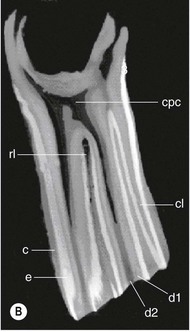

Technical principles

CT is a cross-sectional imaging method that uses a rotating X-ray tube and detector system located in a gantry for image acquisition. When the narrow X-ray beam passes through a selected plane of the body, it is partially absorbed when it passes through tissues with different attenuation coefficients (density). Each tissue is assigned a value that represents its attenuation coefficient. Computerized reconstruction programs are used to assign a gray scale value that correlates to the attenuation value of the tissue being imaged.32 Different algorithms can be used for image reconstructions.33 Each CT instrument manufacturer offers algorithms specifically designed for their individual hardware. For equine dental imaging, a soft tissue algorithm is useful for imaging of the soft tissue structures, followed by a reconstruction in a bone algorithm (high resolution) from the raw data, to allow detailed evaluation of dental and bony structures. The acquired sectional images can be reformatted in various two-dimensional planes or three-dimensional models (Fig. 13.51).